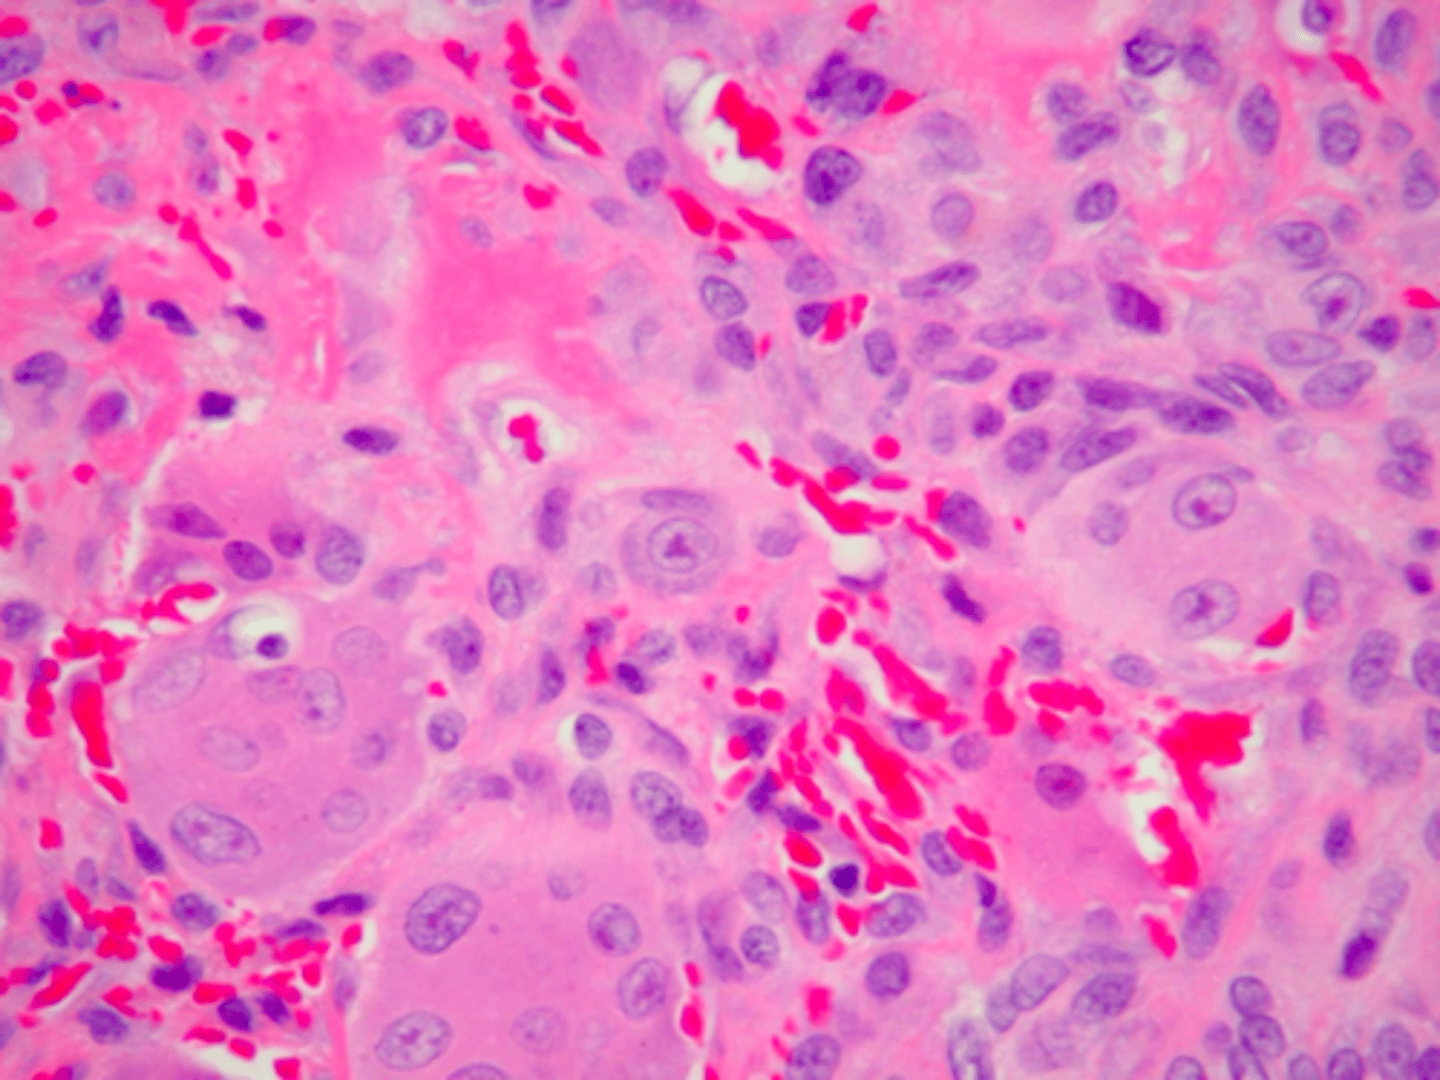

Peripheral Giant Cell Granuloma (PGCG)

patient presents with a purplish, slightly ulcerated nodule on the facial aspect of the maxillary gingiva. Histopathologic features show Multinucleated giant cells with up to several dozen nuclei, hemorrhage and hemosiderin. What do you suspect?

Peripheral Giant Cell Granuloma (PGCG)

Multinucleated giant cells with up to several dozen nuclei, hemorrhage and hemosiderin is associated with what pathology?

local excision down to bone